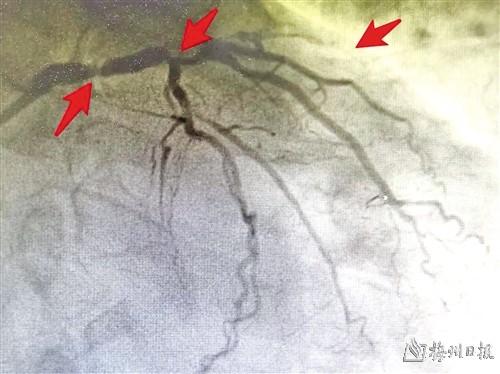

颈动脉狭窄段

前段时间,梅州市人民医院心脏血管外科收治了一位74岁男性患者,详细检查发现,该患者的病情非常棘手,心脏血管以及脑部供血的两条颈动脉已经严重狭窄,同时还合并有贫血、慢性肾功能衰竭、糖尿病、高血压等多种基础疾病,面临着心梗、脑梗双重风险。

据了解,整个手术用时6小时,先剥脱颈动脉内膜,打通1条脑部供血通道,解除脑梗风险,再进行心脏的冠脉搭桥手术,架起3条心脏供血桥梁,解除心梗风险。一台手术同时打通了给心脏和脑部供血的4条主要血管,完美实现了心脑同治。在医院重症监护团队的细心照护下,患者术后5天即下床活动,恢复良好,不久后康复出院。